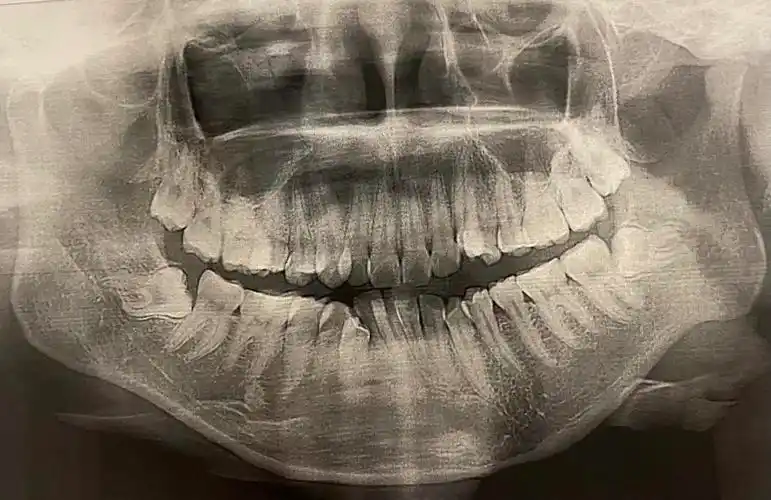

牙片鉴赏有拔过埋伏智齿的uu吗能否分享一下经验

进来了就发一个牙片纪念一下我两个全包围横向阻生牙